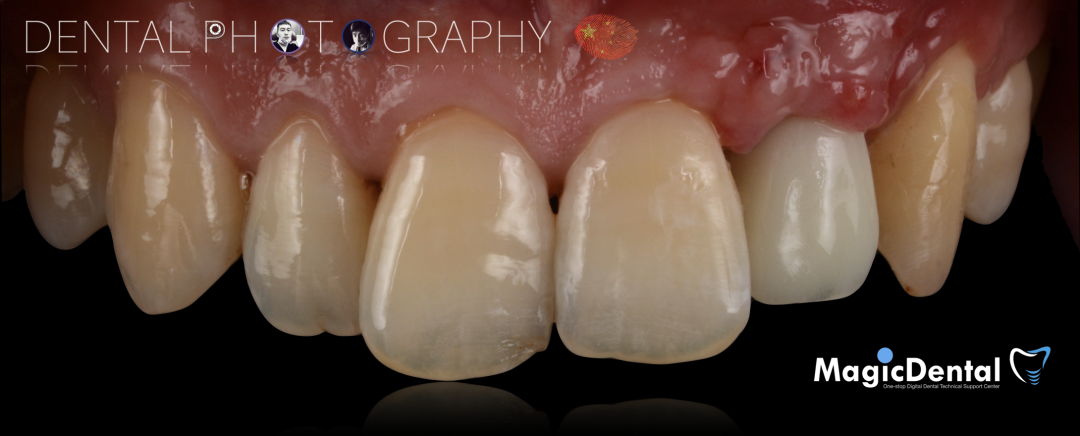

患者术前口内照片

40岁男性患者。

主诉:左上前牙缺失求修复。

现病史:患者因外伤导致前牙松动半年之久,两个月前于外院拔除左上前牙,现自觉不美观来我院就诊。

既往史:既往体健,无其他系统病史,否认重大疾病史,有口腔拔牙史。口腔检查:口腔卫生良好,牙周状况良好,22缺失,缺失间隙约7mm,CT显示缺失牙位置唇颚侧骨壁薄,无对颌伸长,邻牙无移位,上下前牙呈深覆 ,38、48近中阻生。

术后三个月口内正面像

术前术后对比